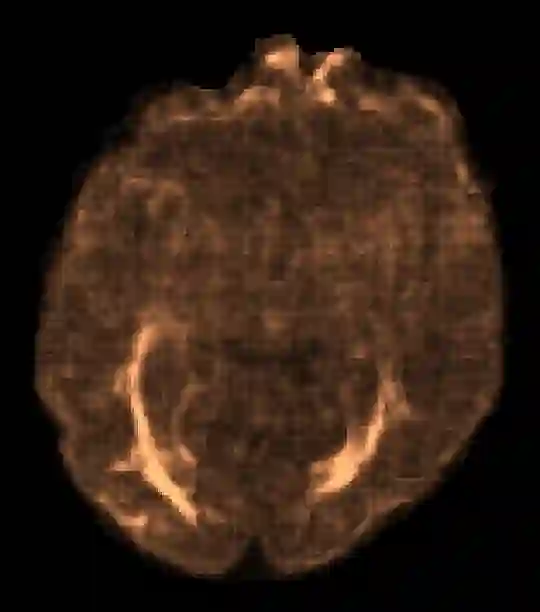

In machine learning, novelty detection is the task of identifying novel unseen data. During training, only samples from the normal class are available. Test samples are classified as normal or abnormal by assignment of a novelty score. Here we propose novelty detection methods based on training variational autoencoders (VAEs) on normal data. Since abnormal samples are not used during training, we define novelty metrics based on the (partially complementary) assumptions that the VAE is less capable of reconstructing abnormal samples well; that abnormal samples more strongly violate the VAE regularizer; and that abnormal samples differ from normal samples not only in input-feature space, but also in the VAE latent space and VAE output. These approaches, combined with various possibilities of using (e.g. sampling) the probabilistic VAE to obtain scalar novelty scores, yield a large family of methods. We apply these methods to magnetic resonance imaging, namely to the detection of diffusion-space (q-space) abnormalities in diffusion MRI scans of multiple sclerosis patients, i.e. to detect multiple sclerosis lesions without using any lesion labels for training. Many of our methods outperform previously proposed q-space novelty detection methods. We also evaluate the proposed methods on the MNIST handwritten digits dataset and show that many of them are able to outperform the state of the art.